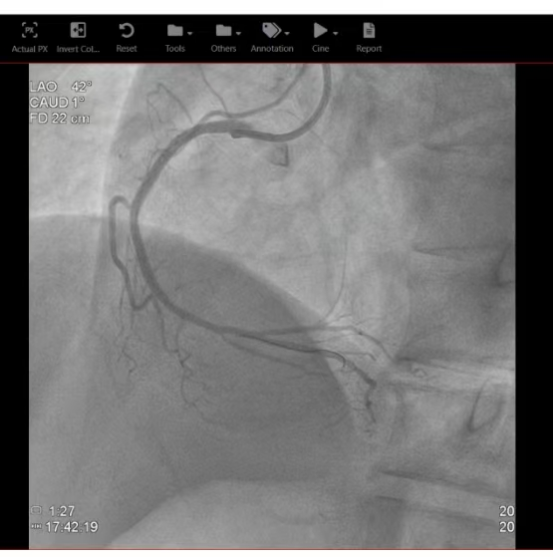

在完成必要的术前准备以及沟通后,由急诊科直接转运至心脏导管室,由心内科刘茂月副主任医师主刀,医护团队凭借娴熟的技术,快速通过导丝、球囊扩张,成功于病变处精准植入两枚药物洗脱支架,血流瞬间恢复,患者的心脏得到了及时、有效的再灌注。手术过程顺利,术后患者生命体征逐渐趋于平稳。